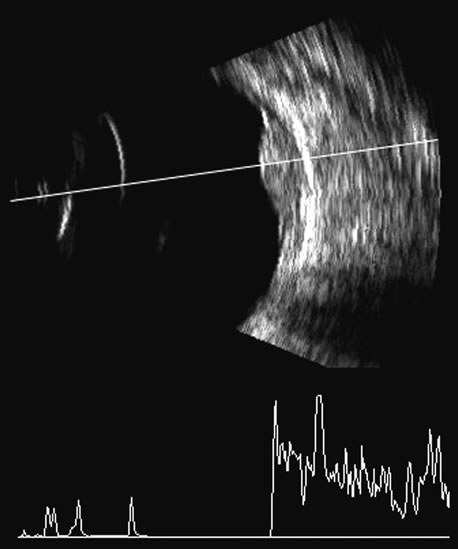

Malignant melanoma varies in its ultrasound presentation from a relatively homogeneous to heterogenous lesion on B-scan. The typical uveal melanoma absorbs sound so that the posterior section is relatively less echoic than the anterior aspect, producing a gradually decreasing amplitude, often to baseline on the A-scan (Fig. 21).

Melanomas also have varying amounts of melanin, a highly acoustically reflective pigment. As noted, melanomas characteristically show high reflectivity anteriorly, with decreasing reflectance as the sound traverses the tissue. This produces the decreasing amplitude posteriorly in the tumor seen on A-scan and gray-scale B-scan. This effect often enhances the anterior scleral boundary. The posterior tumor border is thus measured as the first “rising” echo from the tumor decline, and it is most easily seen and accurately identified on B-scan.27 Metastatic carcinoma is more heterogeneous, producing a more uniform A-scan amplitude of roughly 50% to 80% of the “scleral” echo amplitude (see below) behind the tumor (Fig. 22). Hemangioma is a very highly reflective tumor with high amplitude all the way through the tumor of 80% to 100% of scleral echo amplitude (Fig. 23). The differentiation of tumor tissues is made possible by differences in cellular organization and concentration.29 Acoustically, these are termed as differences in backscattering properties.30–32 A homogeneous solid tissue, such as the lens or the optic nerve, may present few or no echogenic discontinuities and thus appear anechoic and cyst-like. (An echogenic discontinuity is technically an acoustic impedance mismatch in which the acoustic impedance is the product of the density and the speed of sound in each tissue.) A fluid–smooth tissue boundary has a high mismatch or discontinuity and thus produces a high-amplitude echo. A hemangioma with alternating blood- and tissue-lined sacs thus produces a solid-appearing tissue with high-amplitude echoes seen at all depths of the tissue. A metastatic tumor is nearly always a very heterogeneous tissue with randomly organized clumps of similar cells bounded by strands of vessels, necrotic areas, and connective tissue, thus producing a pattern of moderately high-amplitude sustained echoes. To provide a meaningful, reproducible standard of comparison, we use the scleral echo—that is, an echo behind the tumor—for comparison. We believe that the scleral echo generally is highest at the posterior sclera–Tenon's boundary; whereas Ossoinig has stated that the high amplitude echo is at the anterior scleral boundary.28,33 This school (standardized echography) also recommends a tissue velocity for melanoma of 1550 m/sec34,35 compared with the value of 1660 m/sec that we recommend. These differences can produce significant variations in measurement of tumor height, depending on the interpretive methodology used. The velocity of 1550 m/sec gives a smaller tumor height than that of 1660 m/sec, wheras the inclusion of scleral thickness may add 1 to 2 mm to the tumor height when standard echography is used. While this does not affect comparisons of tumor growth, it has a significant bearing on comparisons of data from various investigators.27 On B-scan, the invasion or replacement of the choroid by tumor is of diagnostic importance. Subretinal hemorrhage rests on a smooth curve of the posterior poles; whereas melanoma may replace the choroid, producing an “excavated” pattern.36 A completely dislocated lens can also emulate a tumor but can be differentiated by clinical findings and by having the patient move his or her eye during the examination, which causes lens displacement (Fig. 24).